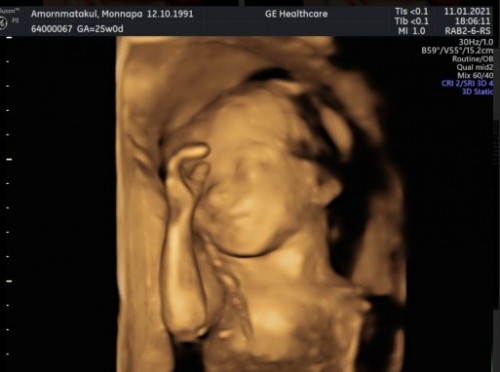

25เมษาค่ะตอนซาว33+1 หนัก2700 แย้วว

35+3 น้องผู้หนัก2200ค่ะ คลอด14เมษา

25 เมษา 33+2 แล้วคะ